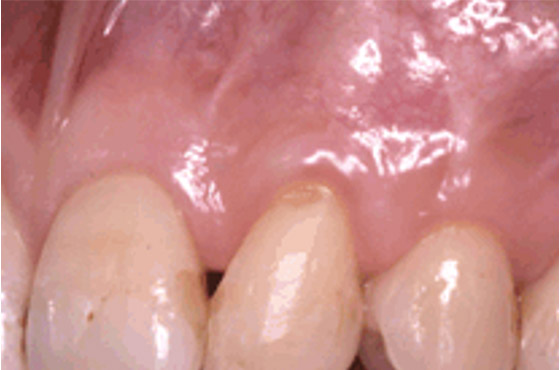

歯周病が進むと、歯肉が退縮して歯が長くなったように見えてしまいます。

この状態を改善できる治療法が「歯肉移植術」です。上あごからご自身の歯肉を切り取り、患部に移植することで、退縮した歯肉を回復させることができます。